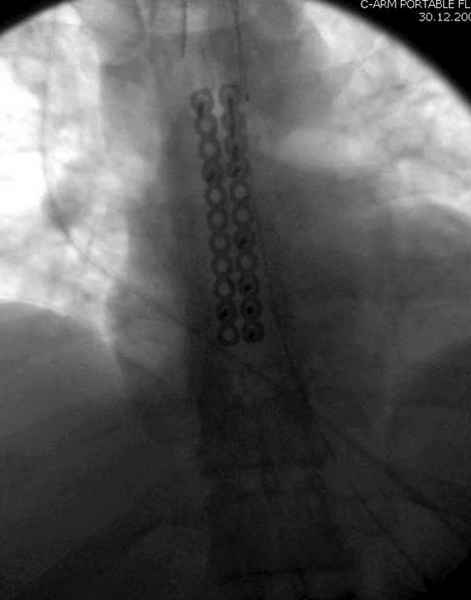

А простые посттравматические ложные суставы грудины приходилось оперировать с ограничителем сверла и с фиксацией 2.4 мм пластинами с угловой стабильностью.

Кардиохирурги, обычно, шьют грудину танталовыми скрепками аппаратом. Если у Вас такой случай, то я делаю "классический" остеосинтез проволокой, иногда подкладываю шайбы, чтобы не прорезалась. А вот если ложный сустав возник после адекватного остеосинтеза тогда сложнее - либо из болт-стяжек надо что-то "собирать" либо спицы и петлю по Веберу (как при остеосинтезе надколенника)